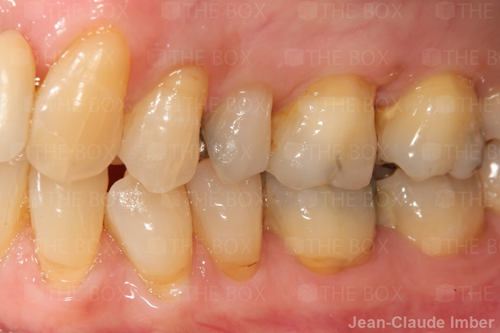

A new case was made public by Jean-Claude Imber check it out here.